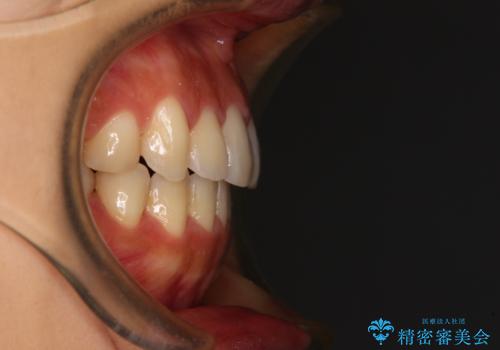

- 飛び出した前歯と口元の突出感を気にして来院された患者様です。

奥歯の咬み合わせを見ると、上顎が下顎に対して相対的に前方にありました。

口元の突出感を改善するためには、上顎臼歯を後方に移動させた咬み合わせにする必要があります。

インビザライン単体で改善することも可能ですが、達成する可能性が高くないため、カリエールディスタライザーという補助装置を併用して、より確実性を上げることとしました。

奥歯の咬み合わせを改善しながら、並行してインビザラインで歯列を整えることとしました。